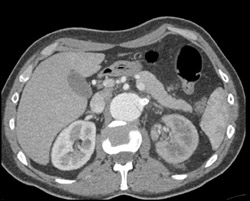

Diagnosis

Decreased Left Renal Function